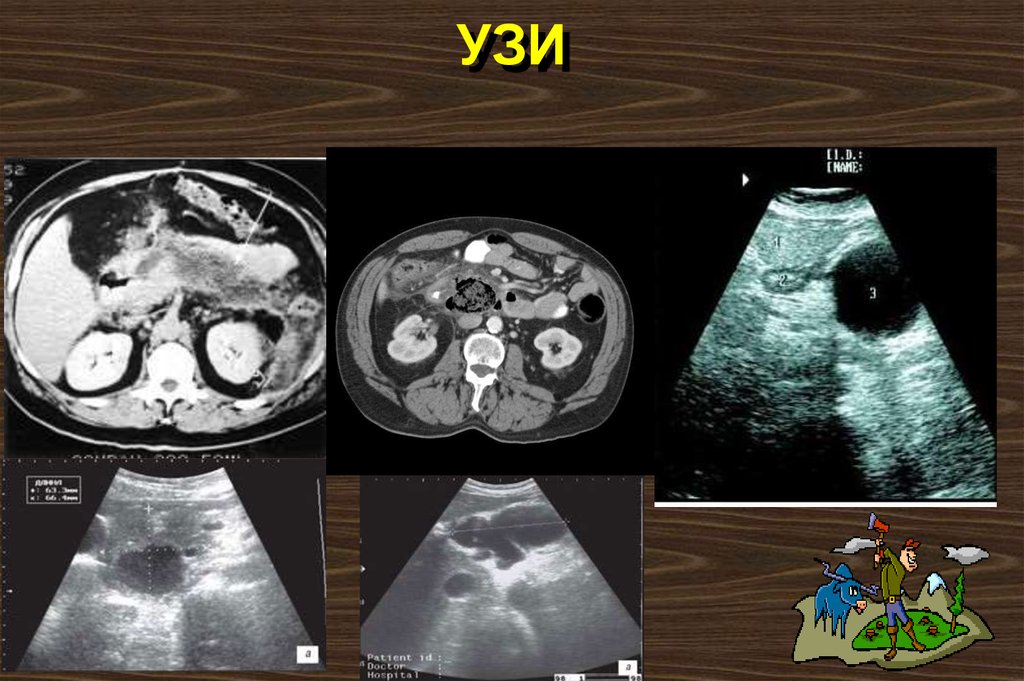

УЗИ

Показания к КТ

КТ